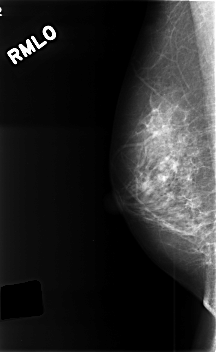

ics_version 1.0 filename C-0385-1 DATE_OF_STUDY 20 5 1996 PATIENT_AGE 40 FILM FILM_TYPE REGULAR DENSITY 2 DATE_DIGITIZED 9 11 1998 DIGITIZER LUMISYS LASER SEQUENCE LEFT_CC LINES 4464 PIXELS_PER_LINE 2872 BITS_PER_PIXEL 12 RESOLUTION 50 OVERLAY LEFT_MLO LINES 4432 PIXELS_PER_LINE 2856 BITS_PER_PIXEL 12 RESOLUTION 50 OVERLAY RIGHT_CC LINES 4560 PIXELS_PER_LINE 2776 BITS_PER_PIXEL 12 RESOLUTION 50 NON_OVERLAY RIGHT_MLO LINES 4576 PIXELS_PER_LINE 2808 BITS_PER_PIXEL 12 RESOLUTION 50 NON_OVERLAY |